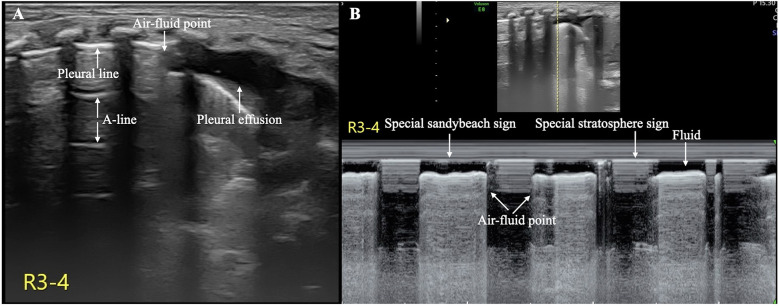

目前,肺超声(LUS)在世界范围内广泛用于诊断新生儿气胸(PTX)和胸腔积液等疾病,这两种疾病都是新生儿期常见的疾病。然而,两种情况并存或同时发生,即气胸积液,在临床上比较少见。超声可提供可靠的诊断,并可用于指导和监测适当的治疗。在这个病例报告中,我们描述了一个新的超声征象,气液点,我们建议作为诊断新生儿气胸的特殊征象。

Currently, lung ultrasound (LUS) is widely used worldwide for the diagnosing conditions such as neonatal pneumothorax (PTX) and pleural effusion, which are both common conditions during the neonatal period. However, the coexistence or simultaneous occurrence of both conditions, namely, hydropneumothorax, is relatively rare in clinical practice. Ultrasound enables a reliable diagnosis and can be used to guide and monitor appropriate treatment. In this case report, we describe a new ultrasound sign, the air-fluid point, which we propose as a specific sign for the diagnosis of neonatal hydropneumothorax.